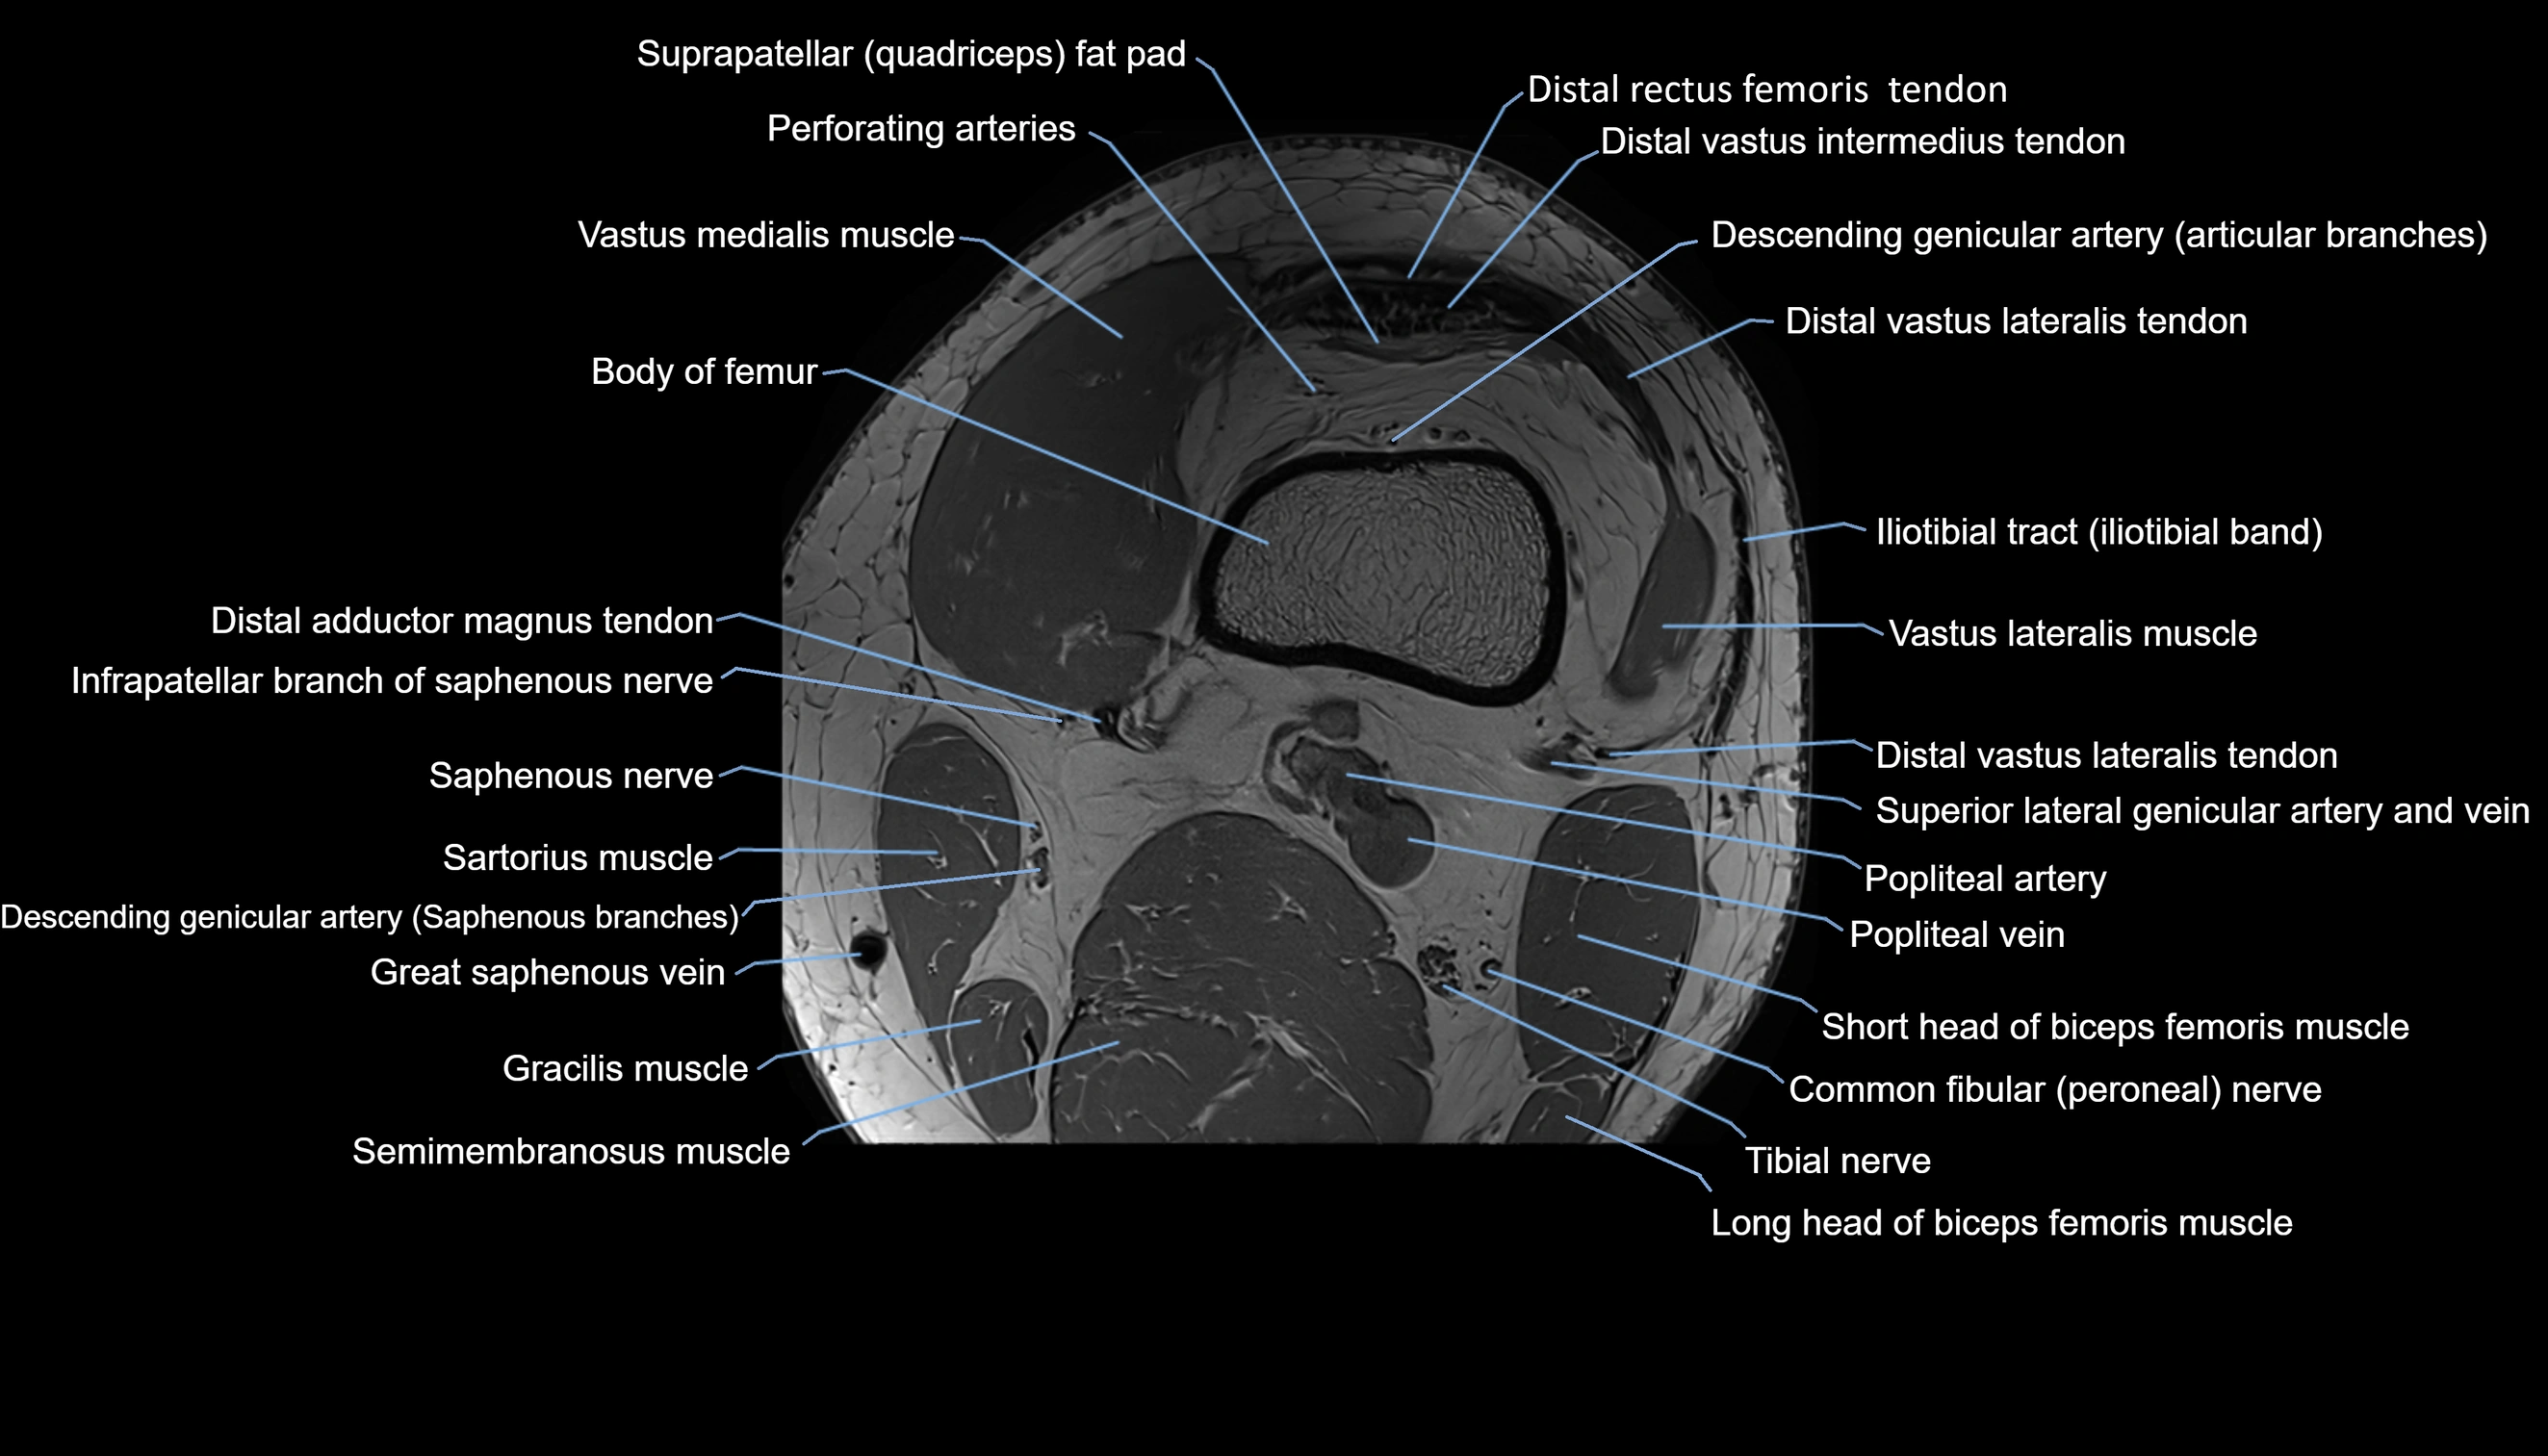

- Perforating Arteries (Knee joint)

- Popliteal artery

- Popliteal vein

- Saphenous nerve

- Sartorius muscle

- Semimembranosus muscle

- Tibial nerve

- Vastus lateralis muscle

- Vastus medialis muscle

- great saphenous vein